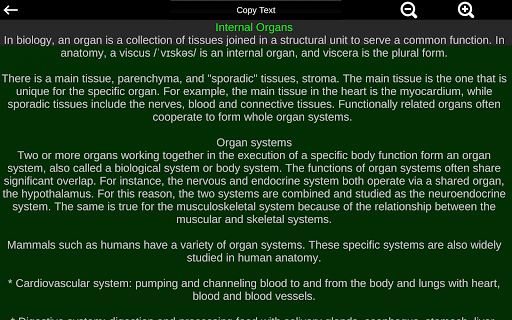

Internal Organs in 3D Anatomy لـ Vodafone Smart N9 Lite

Internal Organs 3D Anatomy 3.4

Internal Organs 3D Anatomy 3.1

Organs 3D Anatomy 2.0.12

يمكنك هنا تنزيل ملف حزمة تطبيق أندرويد "Internal Organs 3D Anatomy" الخاصة بجهازVodafone Smart N9 Lite مجانًا، نسخة ملف حزمة تطبيق أندرويد - 3.4 للتحميل على Vodafone Smart N9 Lite اضغط ببساطة على هذا الزر. إنه سهل وآمن. نحن نقدم فقط ملفات حزمة تطبيق أندرويد الأصلية. إذا انتهكت أية مواد موجودة في الموقع حقوقك قم بإبلاغنا من خلال